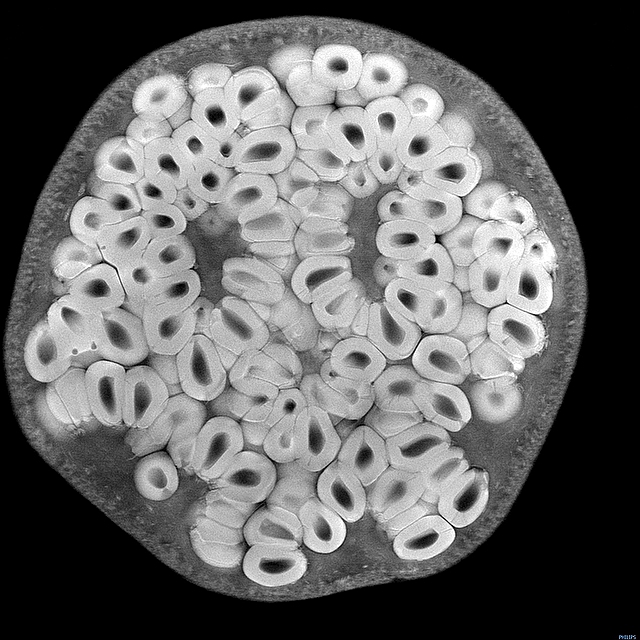

0 a, H7 }9 Q$ h下面是埃里森制作的GIF图,从上往下依次是杨桃、草莓和抱子甘蓝(左边彩图来自Shutterstock.com),最后是一张洋葱的3D图。% i! I: g6 d. x6 S: m- o9 o